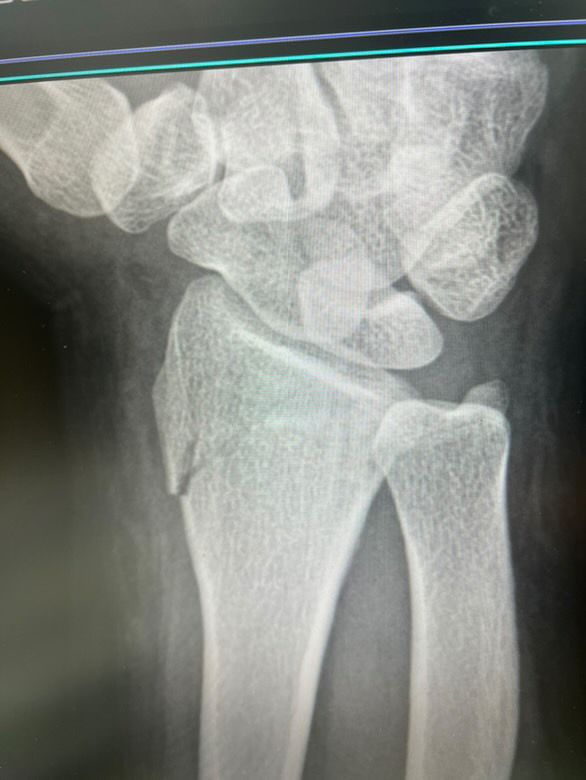

• 2번 째 사진

• 엑스레이 사진을 보았을 때 요골 골절이 있어 보입니다. 해당 엑스레이 사진만 놓고 정확하게 어떻다 이야기를 하기는 어렵습니다만, 개인적으로 보기에도 수술적 치료가 필요할 것으로 사료됩니다. 손목 같은 경우 많이 사용하는 부위이며 기능이 잘 유지되도록 하기 위해서는 적극적으로 치료가 필요합니다.